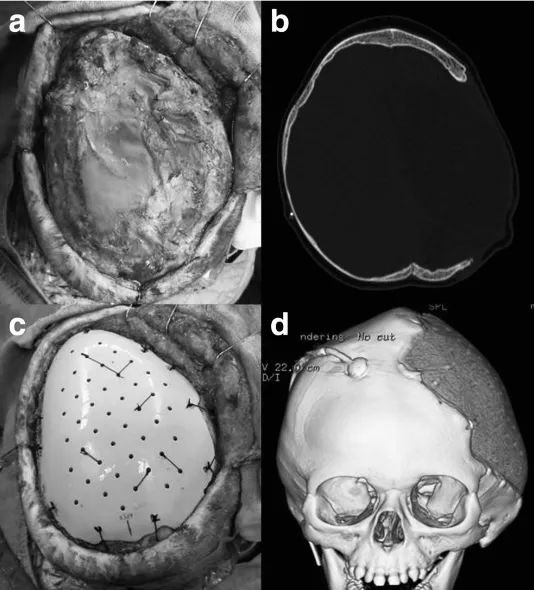

塑料聚合物(包括多孔聚乙烯和聚醚醚酮(PEEK))在多种现代假体设置中展现出优势。多孔聚乙烯被认为允许理论上的骨内生长和血管化,尽管其成骨传导性曾受到质疑。在儿童中,该材料已在小型临床系列中得到应用,效果良好,但受限于随访时间短暂(平均 3.6 个月)。PEEK 是一种惰性、轻质且高度生物相容的材料,但缺乏成骨传导性。PEEK 在成人中的应用迄今提供了良好的数据,但在儿童群体中的文献数据仍有缺失(图 4)。

图 4:一名 11 个月大婴儿的大脑半球颅骨缺损(a 为术中照片,b 为术前 CT 扫描图),采用定制的聚醚醚酮(PEEK)植入物进行修复(c 为术中照片,d 为术后三维 CT 扫描图)。